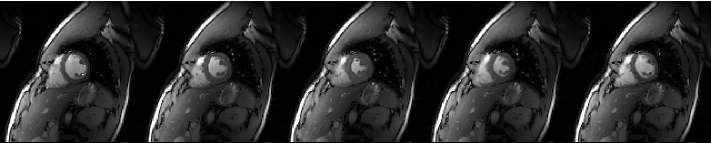

Refer to caption

Figure 2: Frames 1, 4, 7, 10, 12 of the cine dataset

Experiments are conducted on a 2D cardiac MRI dataset acquired on a 3T Siemens Trio scanner using a 32-coil matrix body array. Fully sampled data were acquired using a 128×128128128128\times 128 matrix (FOV = 320×320320320320\times 320 mm) and 22 temporal frames. The fully sampled data is then retrospectively undersampled by a factor of 8 using a different variable density random undersampling along vertical axis for each time point as shown in Figure 1. The data is normalized so that the reconstruction of the fully sampled data leads to images with maximum intensity of 1. The sample frames from reconstruction of the fully sampled data can be seen in Figure 2. The subsampled data is reconstructed with Algorithm 1 and Algorithm 2 using the SVD method to compute the term (μ𝐈+𝐇𝐇)1superscript𝜇𝐈superscript𝐇𝐇1(\mu{\mathbf{I}}+{\mathbf{H}}^{\prime}{\mathbf{H}})^{-1} and setting temporal DFT as 𝚿𝚿{\mathbf{\Psi}} and temporal TV as 𝐑𝐑{\mathbf{R}} respectively. The same λ𝜆\lambda value that results in good quality reconstruction is used for all the tested algorithms (λ=0.002𝜆0.002\lambda=0.002).